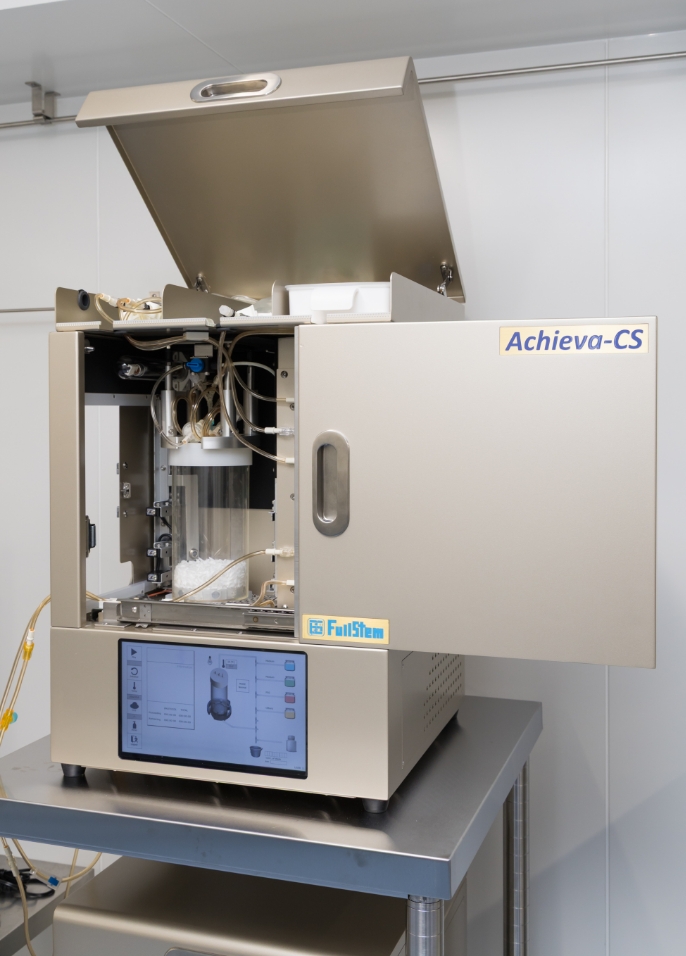

CPC(細胞培養加工施設)

当院は、CPC(細胞培養加工施設)を併設した再生医療専門クリニックです。

高品質な細胞・培養上清液を、自社施設で一貫して管理・提供することで、安心で質の高い医療をお届けします。